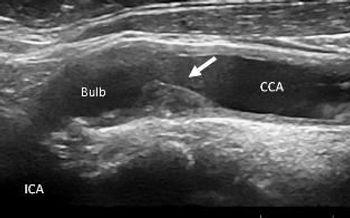

Patients with rheumatoid arthritis are at considerably increased risk of asymptomatic carotid artery disease, but standard scores have proven poor predictors of their actual cardiovascular risk. Special vigilance is warranted for these patients.